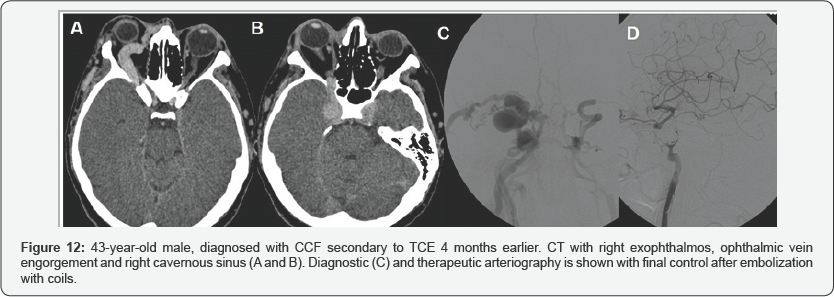

The initial treatment of three patients was balloon occlusion, requiring two of them to be closed with coils in a second time, due to the persistence of low flow CCF. In the two remaining patients, the initial treatment was with coils (Figure 11 & 12).